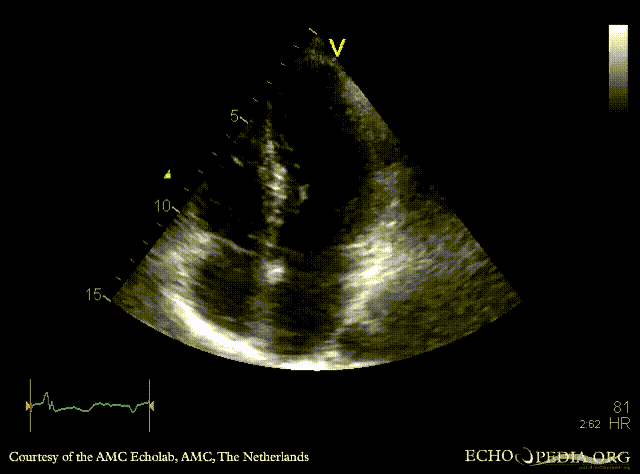

E00502.gif E00503.gif

PLAX: concentric hypertrophy of left ventricle, SAM of AMVL PLAX with Color Doppler: high velocity turbulent flow in LVOT